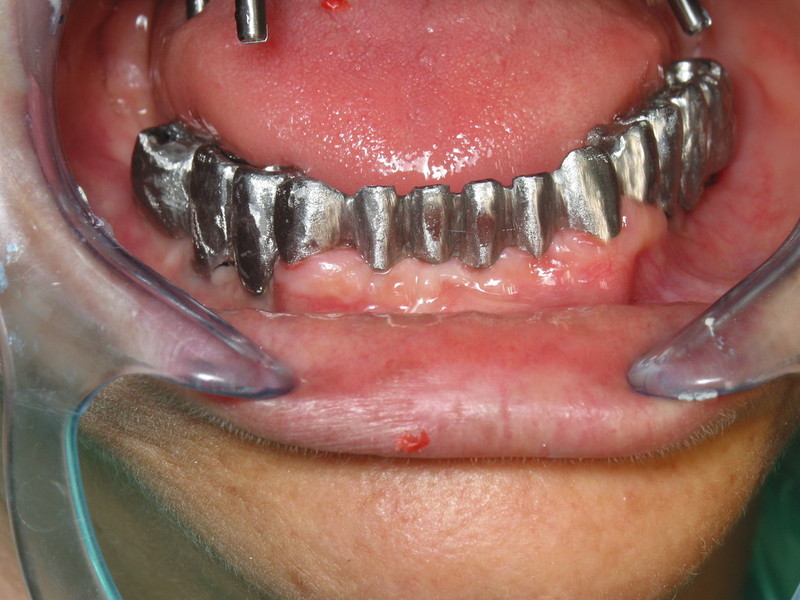

Paciente afectada de Enfermedad Periodontal Avanzada, en ambos maxilares.

En el maxilar superior, perdida ósea vertical generalizada de más de 5 mm, movilidad grado I y grado II.

Tinciones melánicas en la encía.

En maxilar inferior , enfermedad periodontal avanzada del adulto, con perdida de inserción ósea y ligamentosade 5 mm en casi todas las piezas  a excepción de las piezas31 y 41 incisivos  inferiores, con recesisón gingival de atkins y sullivans grado 2.Con defecto vertical superior a 7 mm.

Decapaje de las manchas de melanina.